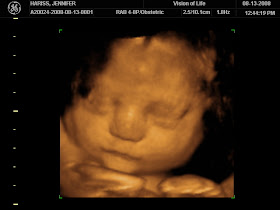

I had my ultrasound at around noon today and baby measured around 36/37 weeks and they estimate his weight to be about 6 pounds! Dr. Keith said he is in the 70% percentile but still not too big to be a concern to me just yet. Whew!! Unfortunately, he is so big and his head is so low that we were unable to get a good picture of him, but I did see his big round belly and little beating heart.